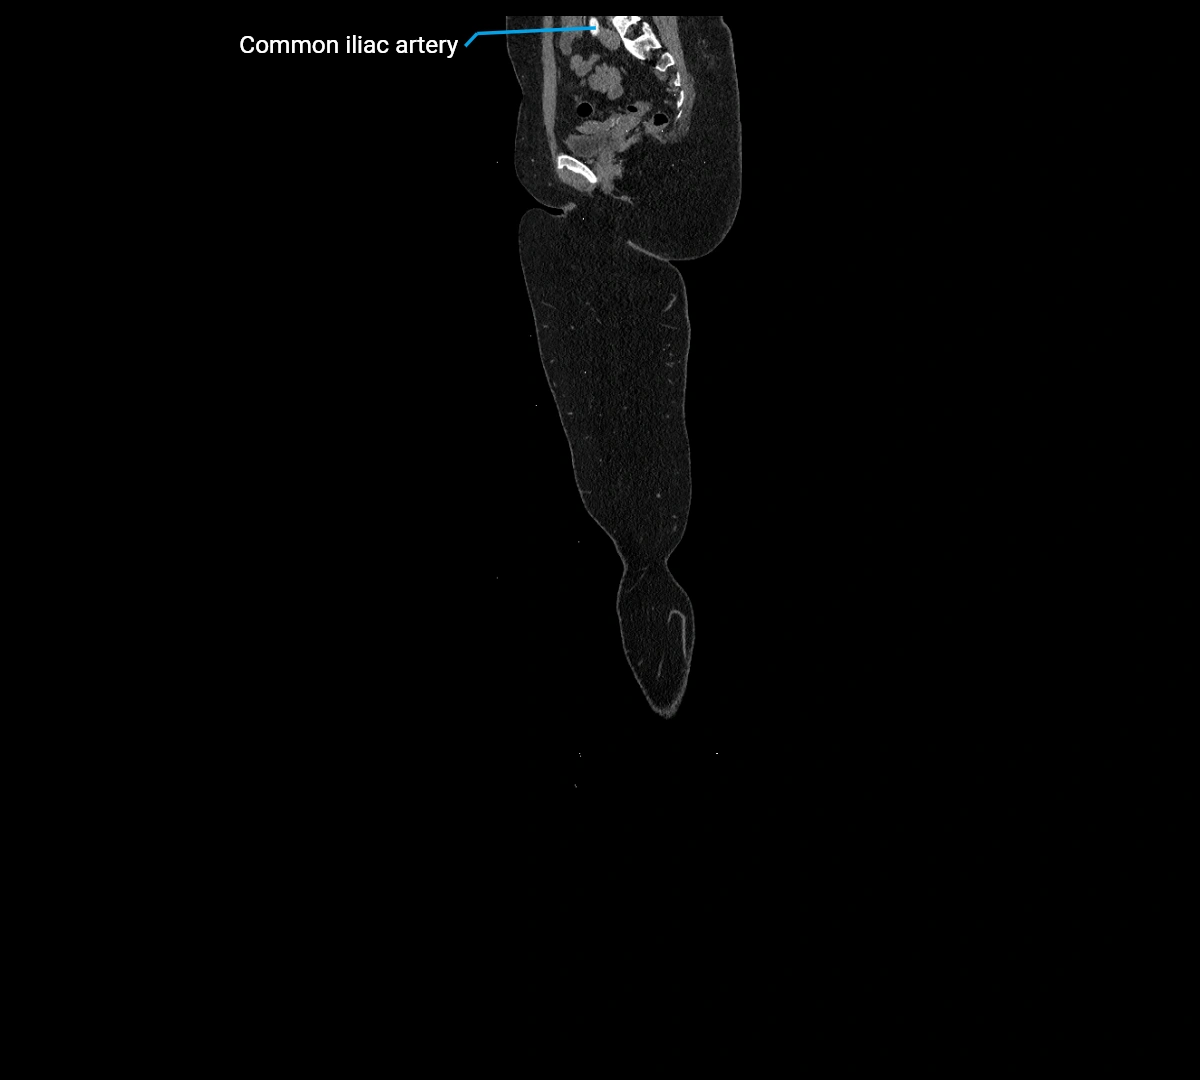

CT Appearance

Non-contrast CT:

• Appears as a tubular soft tissue structure anterior to vertebral bodies

• Calcified atherosclerotic plaques appear as hyperdense foci along the wall

• Useful for screening abdominal aortic aneurysm (AAA) size and mural calcification

Contrast-enhanced CT (CTA):

• Gold standard for abdominal aortic imaging

• Provides excellent detail of lumen, wall, aneurysm, thrombus, and branch vessels

• Multiplanar and 3D reconstructions help in aneurysm measurement, stent graft planning, and dissection evaluation

• Detects acute rupture, traumatic injury, or occlusion with high sensitivity